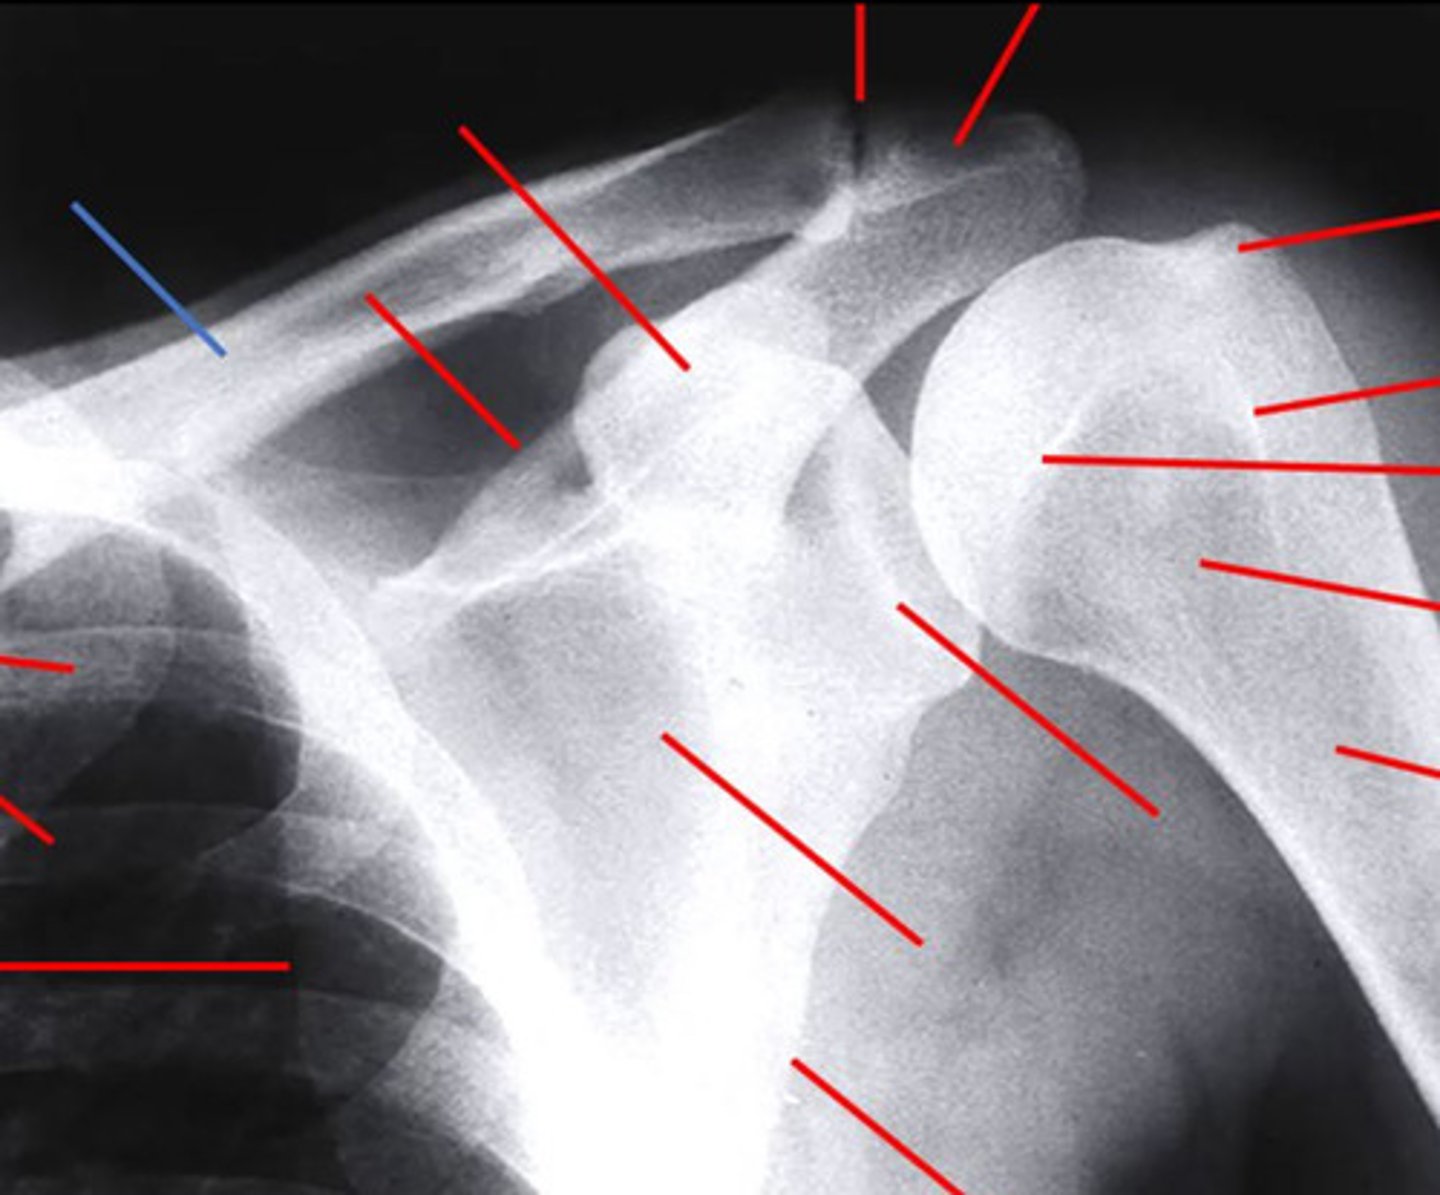

what is the name of this view of the shoulder?

axillary

3 multiple choice options

which structure of the shoulder is highlighted by the blue line in the image?

clavicle